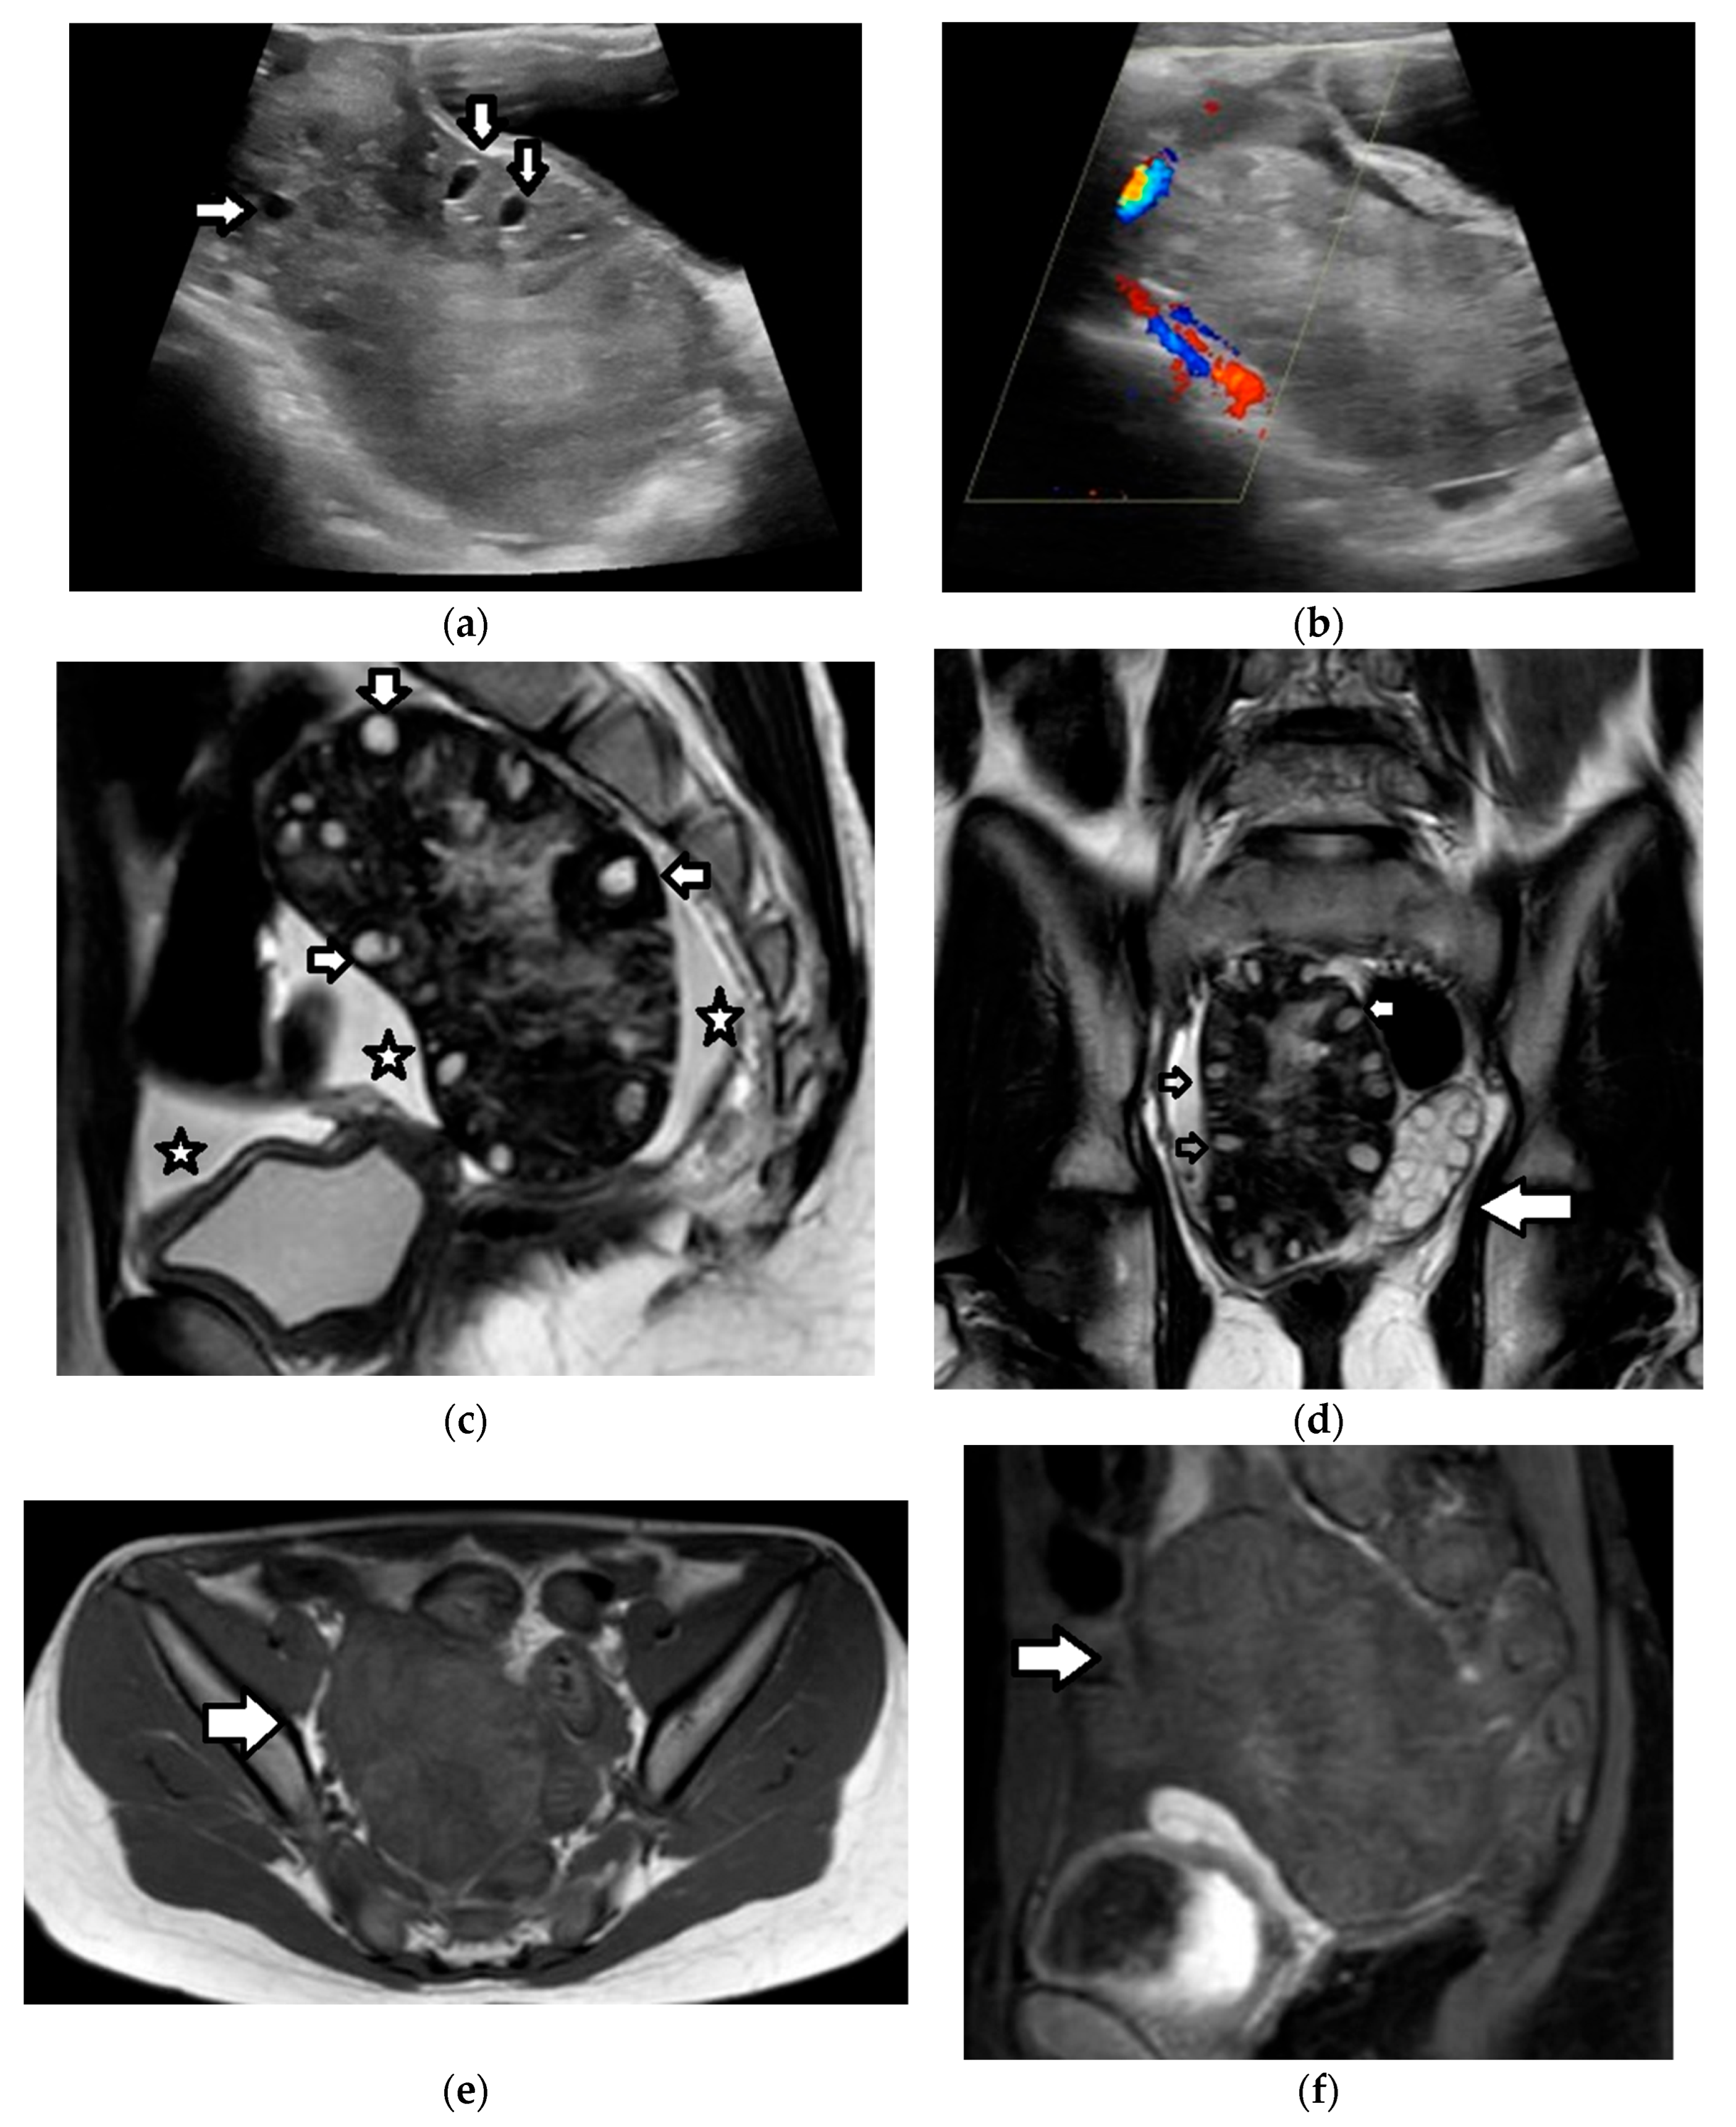

| Juvenile granulosa cell tumor | 75% of SCSTs mean age: 13 years bilateral: 4–5% secretes estrogens: signs of isosexual peripheral precocious puberty or menstrual irregularities secretes androgens: virilization (rarely) possible association with enchondromatosis syndromes: Maffuci syndrome, Ollier disease | malignant often diagnosed at an early stage excellent prognosis recurrence: rare | estrogens androgens (rarely) inhibin, especially inhibin B Müllerian Inhibiting Substance | nonspecific large size (mean diameter, 12.5 cm) multicystic tumor, with solid vascular components MRI

|

| Sertoli–Leydig cell tumor | 15% of SCSTs mean age: 14 years mostly unilateral secretes androgens: virilization secretes estrogens (rarely) association with DICER1 syndrome(moderately and poorly differentiated tumors) possible association with Peutz–Jeghers syndrome | moderately and poorly differentiated tumors: clinically malignant in 10% and 60% of cases, respectively often diagnosed at an early stage favorable prognosis recurrence rate: may be high | increased AFP (occasionally): poorly differentiated tumors with heterologous hepatocyte elements | nonspecific predominantly solid vascular tumor, with numerous peripheral or intratumoral cysts or cystic, with solid components MRI